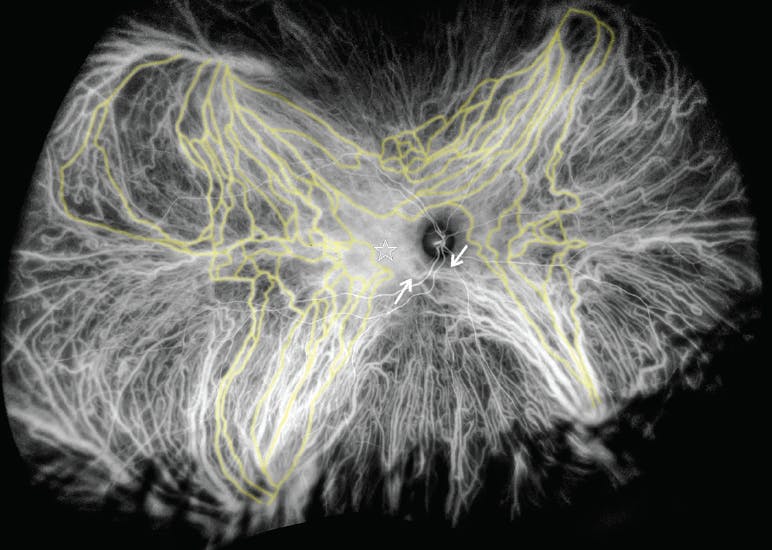

CSC is one condition well-known to cause a thick choroid, likely as an epiphenomenon. Pathophysiologic changes that occur in CSC appear to be present in other diseases, and these findings may help offer a pathophysiologic explanation. For example, a recent study using ICG angiography offered interesting findings in a series of eyes with either CSC or peripapillary pachychoroid syndrome (Figures 1 and 2).9 Ordinarily, the vortex vein systems empty the choroid in a quadrantic fashion. The vortex veins in each quadrant course toward the vortex vein ampulla and exit the eye near the equator. Each system is independent of the others, and there is a watershed zone between them.10 In both CSC and peripapillary pachychoroid syndrome, large anastomotic connections were seen between the vortex vein systems—a finding that was uncommon in control eyes.10 In CSC eyes, these occurred in the central macular region; in peripapillary pachychoroid syndrome, they appeared around the nerve. The same pattern, large intervortex venous anastomoses, was present in eyes with CSC that progressed to neovascularization or polypoidal choroidal vasculopathy.10

Figure 2. This patient has CSC. The ICG angiogram shows the venous drainage, with some of the intervortex venous anastomoses highlighted in yellow. There were vessels from the inferonasal vortex vein system that crossed over the expected vertical venous watershed zone (arrows) but, because there already is significant leakage in the submacular choroid (star), anastomoses could not be identified.